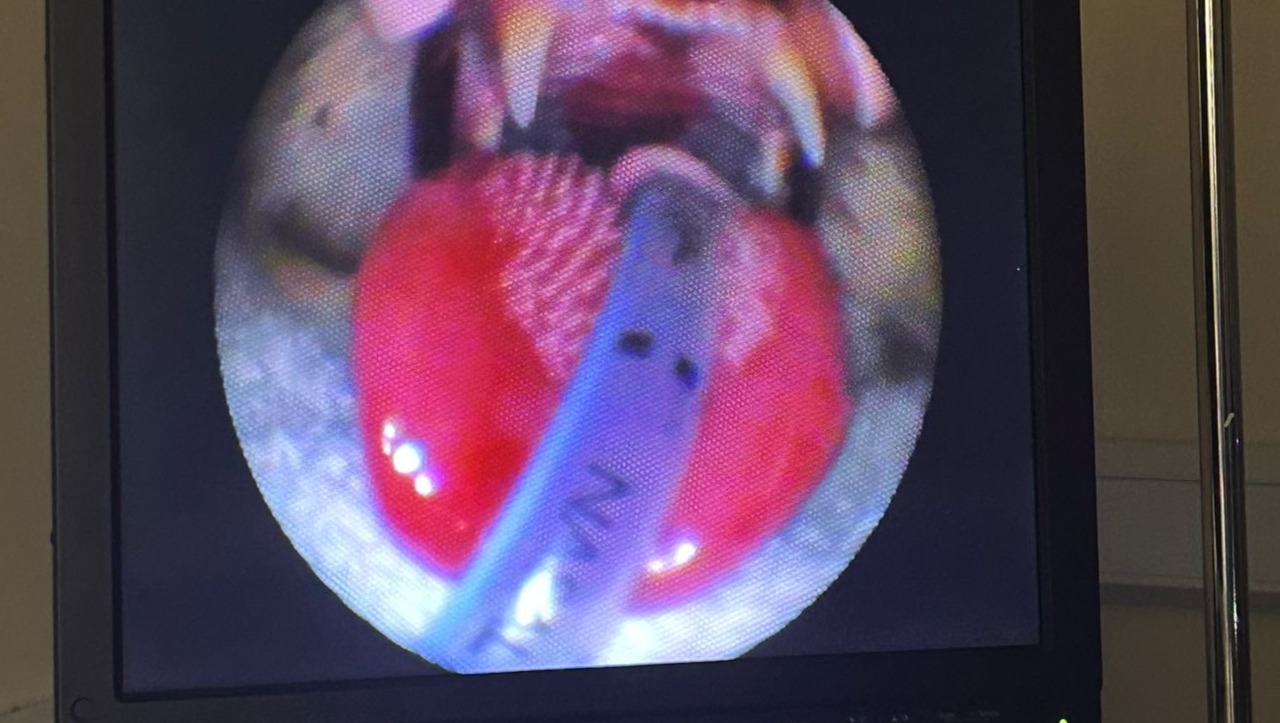

Mr b had ingested something toxic and burnt all his mouth needed emergency care. We spent £2,803.96 on his emergency care , endoscope and feeding tube . He still needs more care so will be more bills